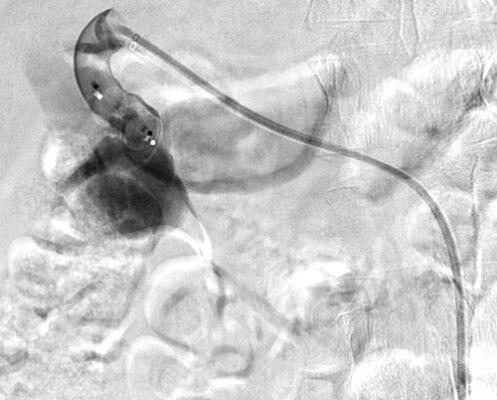

64 year old male who presents with right testicular pain, mild right flank pain, and signs of early CHF.

Comment: This patient presented with scrotal pain, right flank pain, and early CHF. Upon review of the imaging, it became clear that all three of these symptoms were related. The renal angiogram demonstrated prompt opacification of the right renal vein and IVC. This appeared to be secondary to an AV fistula that resulted in increased venous pressure, which contributed to the development of a varicocele (through a branch of the right renal vein draining into the right testicular vein before passing into the IVC). In addition, the outflow from the fistula likely increased right heart pressure, leading to his cardiac symptoms.